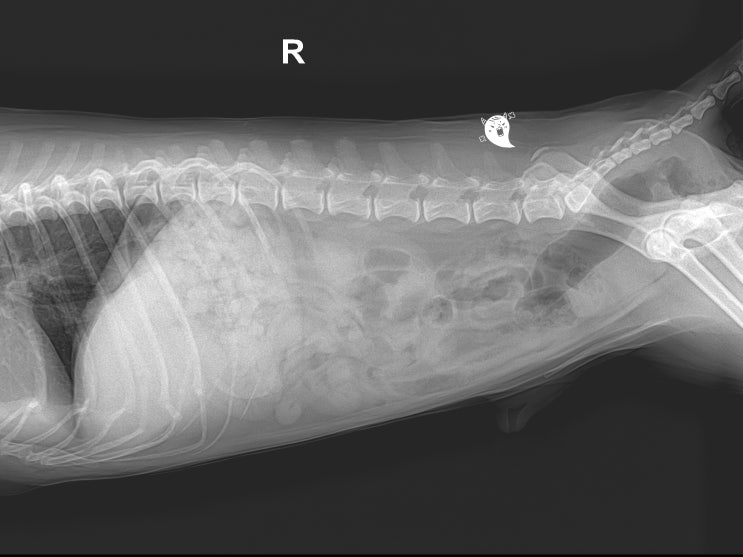

18살 고양이 호흡 이상, 곤란한 이유 / 노령묘 흉수 원인, 치료, 관리법 / 고양이 식욕 감소, 호흡수가 빠른 이유는? / 고양이 유미흉 엑스레이, 치료, 관리하는 방법

안녕하세요~ 굿파파 수의사입니다. 벌써 4 월의 마지막 일요일입니다. 행복한 미소 가득한 하루 보내세요 ...